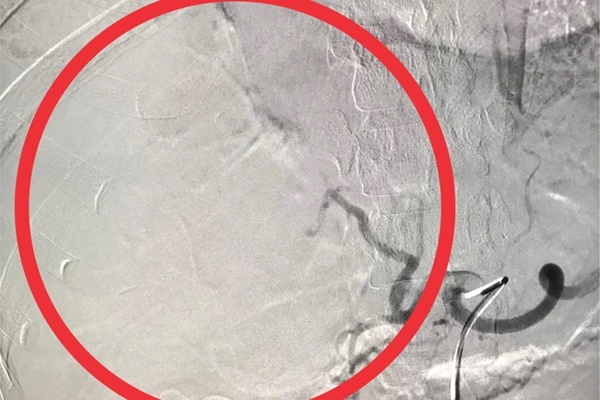

Sau đó, chị L. được chỉ định thực hiện thủ thuật can thiệp chụp và nút mạch cầm máu gan trên hệ thống máy chụp mạch số hóa xóa nền (DSA), kết hợp vật liệu tắc mạch vào động mạch gan phải để tiến hành cầm máu gan vỡ.

Hình ảnh chụp gan bệnh nhân trước khi điều trị...

Và sau khi được điều trị (Ảnh: BV cung cấp).